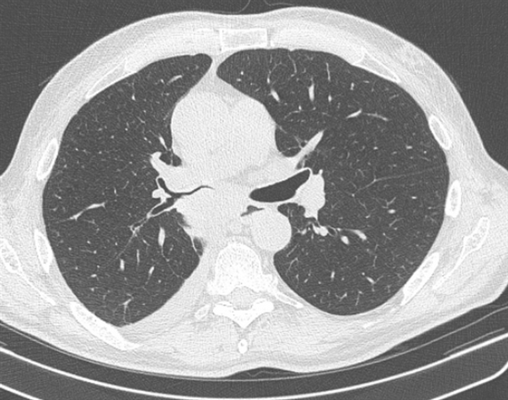

Сканы КТ отличаются более высокой четкостью изображений и информативностью. В ходе компьютерной томографии рентгеновская трубка вместе с чувствительными датчиками совершает несколько оборотов по спиральной траектории, сканируя исследуемую область. Аппарат КТ делает множество сканов толщиной до 1 мм, на основании которых воссоздается трехмерная модель легких, сосудов, органов и костей грудной клетки в высоком разрешении. Таким образом после компьютерной обработки изображений ткани и органы можно исследовать в трех проекциях, эффект наложения теней от органов в случае с компьютерной томографией отсутствует.

Назначить КТ или рентген легких при пневмонии сможет только врач после изучения симптомов, лабораторных анализов, индивидуальной клинической картины пациента. Наличие жидкости или гноя в альвеолах, а также фиброз визуализируется и на рентгенограмме и на сканах КТ. Однако традиционного рентгена при пневмонии I-II степени может быть недостаточно, в то время как на КТ она видна более определенно как «матовые стекла». При атипичной пневмонии и при коронавирусе рекомендуется сделать КТ легких.